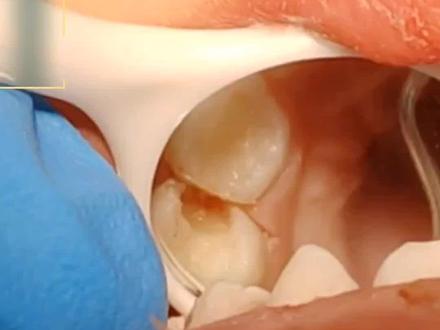

网友求救了,我的蛀牙都补完了,怎么还会疼啊?咱们看啊,这颗牙是不是坏的很大,底部好像都空了,有两个孔?对的,如果这种情况你直接补上,很有可能补完了就会特别疼,或者是以后牙龈上直接肿包了。 那坏到这么深,牙神经早就已经发炎了,不管你之前有没有特别疼过,所以必须要做完善的根管治疗,才能彻底的清理炎症,不用害怕会不会疼,现在的治疗很人性化,都会给打麻药, 那我们要把所有的腐质全部去干净,露出剩余的好牙,上上橡皮杖,就开始进入根管治疗过程了。你有没有发现三个孔,这是根管的入口,牙神经就在里面,所以 随着器械的进去处理啊,里面炎症的牙髓会被清理干净,同时根管的管壁上残留的细菌也会被清理干净,最后要把这个管枪沿四合缝的堵上,材料也就是我们常用的牙胶和壶剂, 最后再用树脂材料把牙恢复如初,这就是完整的根管治疗过程。那如果这位朋友当时就做好完善的根管治疗,也不至于这会哗啦一声八千块钱没了。